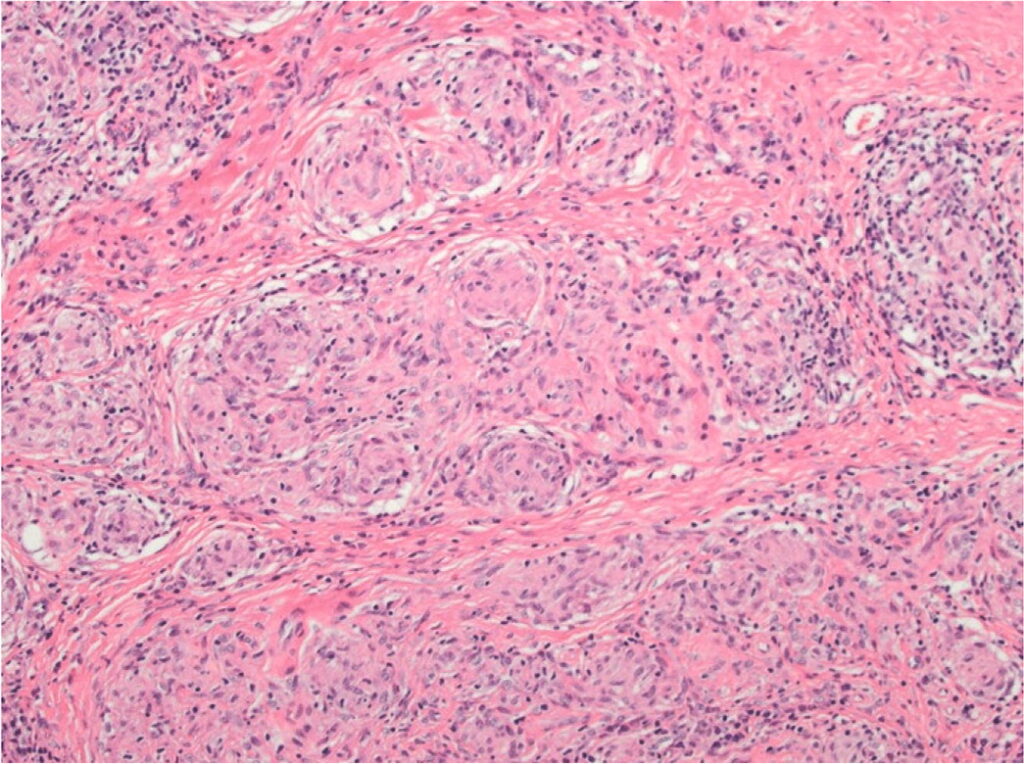

Dal punto di vista istopatologico, il granuloma sarcoideo rappresenta l’unità funzionale della malattia. Esso è costituito da un raggruppamento organizzato di cellule infiammatorie, principalmente macrofagi attivati che assumono un aspetto epitelioide e possono fondersi per formare cellule giganti multinucleate, come le cellule di Langhans.4

Questi aggregati sono tipicamente circondati da una corona di linfociti, con una netta prevalenza di linfociti T helper CD4+, e in misura minore da linfociti B e plasmacellule.5 Un elemento discriminante fondamentale rispetto alla tubercolosi è l’assenza di necrosi caseosa centrale, sebbene in rari casi possano essere presenti minime aree di necrosi fibrinoide.

La dinamica di formazione del granuloma suggerisce un processo di compartimentazione immunitaria, in cui l’organismo tenta di isolare un antigene persistente e non degradabile. Se il processo infiammatorio non si risolve, la persistenza delle citochine profibrotiche prodotte dai macrofagi e dai linfociti Th2 può indurre una transizione verso la fibrosi, portando alla distruzione dell’architettura tissutale originale e alla perdita della funzione d’organo, come osservato nellostadio IV della sarcoidosi polmonare.6 7